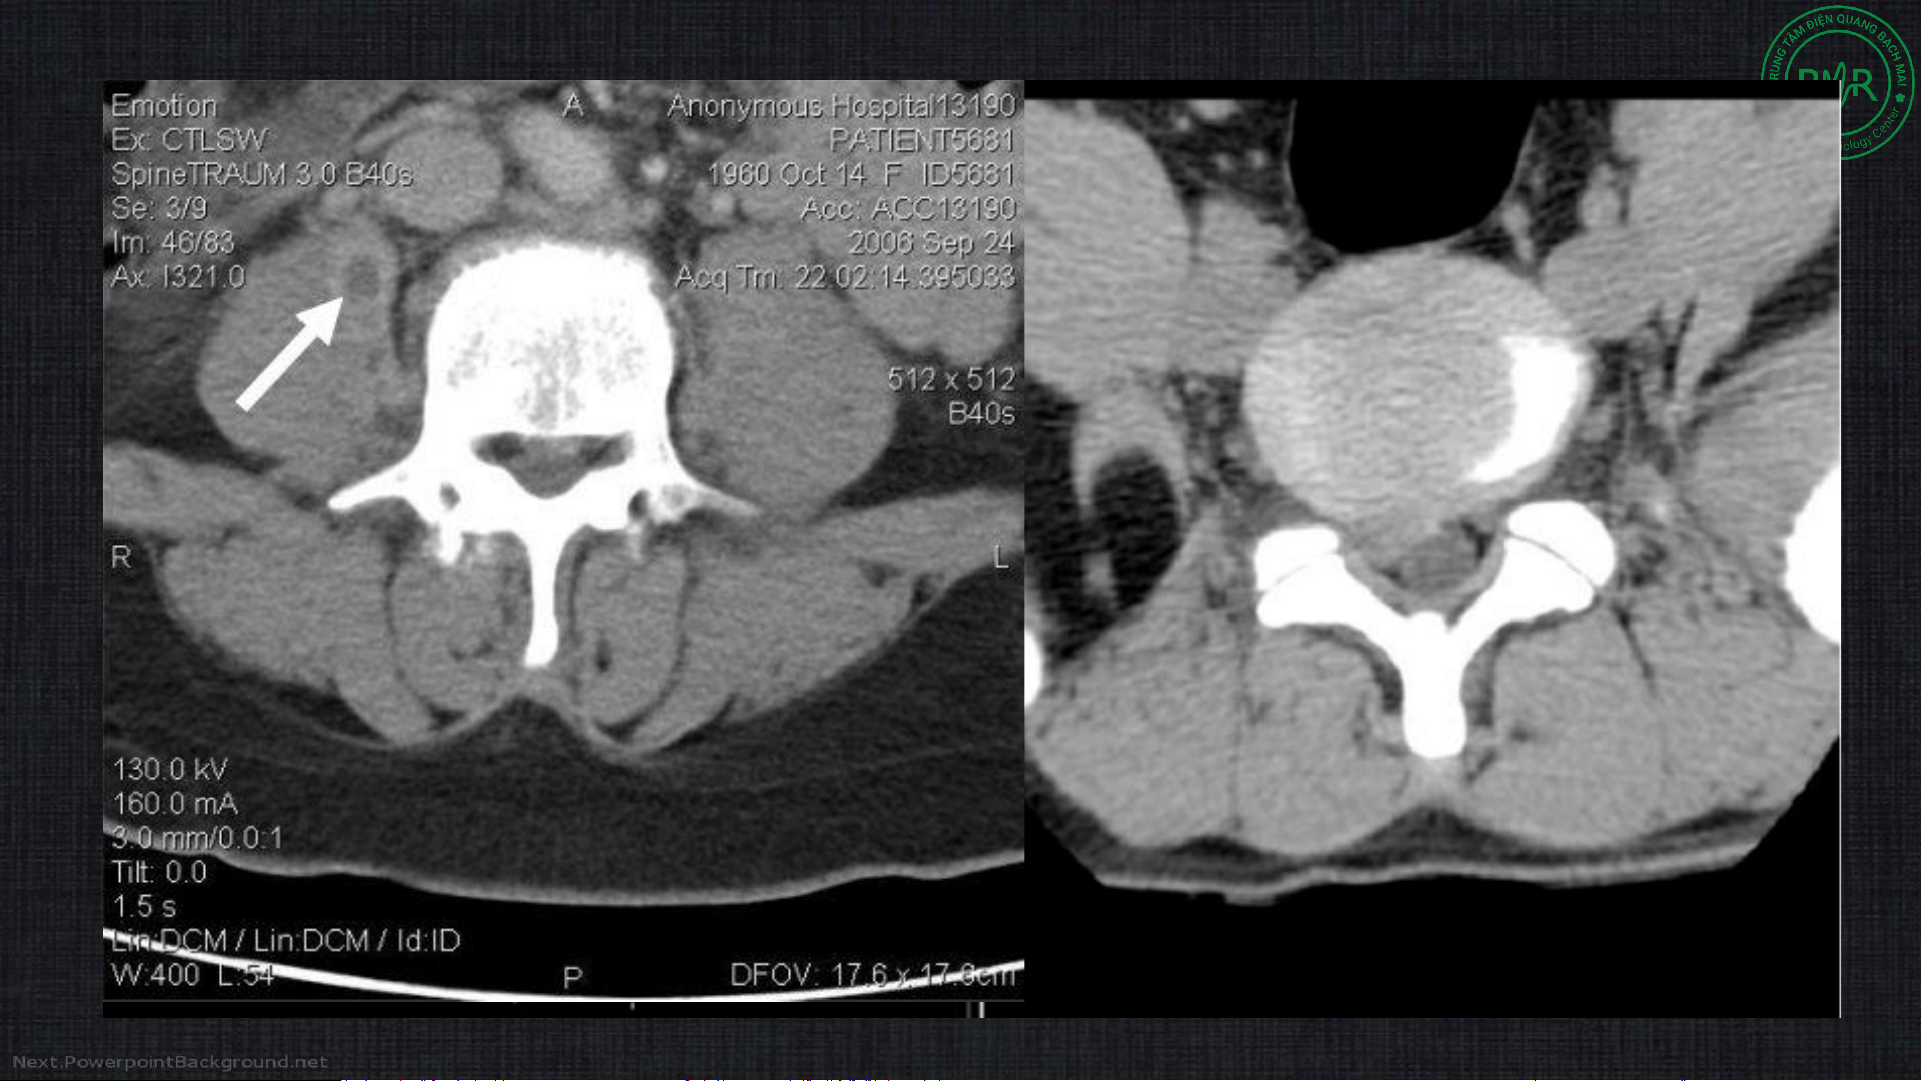

• Cửa sổ xương và phần mềm

• Đánh giá cột sống và cấu trúc xương tốt hơn

• Độ phân giải không gian kém/ nhiễu ảnh do xương → hạn chế đánh giá tủy

sống, phần mềm so với cộng hưởng từ

• Ít xâm lấn, có thể chụp cùng thuốc cản quang trong tủy sống (myelography) Cửa sổ xương Cửa sổ phần mềm Tụ máu NMC Nhiễu ảnh